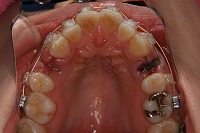

23歳5か月

上顎

上の前歯が出ている事を主訴に来院された、23歳2か月の女性です。診断「下顎骨の後方回転による骨格性上顎前突で開咬を伴う」上顎は両側第1小臼歯、下顎は抜歯をせず治療を行いました。